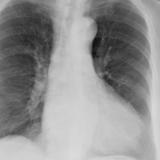

Case 9 Thymoma PA

Date: 04/04/2010

Views: 3176